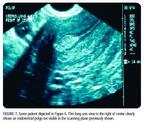

In that study, 280 patients (65%) displayed a thin, distinct, symmetric endometrial echo of 5 mm or less on day 4 through 6, and dysfunctional uterine bleeding was diagnosed (Figure 2). One hundred fifty-three (35%) had SIS. Of these procedures, 44 (29%) were performed because of the inability to adequately characterize and measure the endometrium (Figures 3 and 4) and 109 (71%) were done for endometrial measurement of 5 mm or more. Sixty-one of those patients then had both anterior and posterior endometrial thickness that was symmetric and less than 3 mm, compatible with dysfunctional uterine bleeding. Of the original 433 patients in the study, 58 patients (13%) had focal polypoid masses (Figure 5) that were removed hysteroscopically and confirmed pathologically. Twenty-two patients (5%) had submucous myomas although 148 patients (34%) had clinical and ultrasonographic evidence of fibroids. Ten patients had single-layer measurements of endometrium of more than 3 mm (range 39 mm) during SIS. Of these, five patients had a proliferative endometrium and five had a hyperplastic endometrium. SIS was technically inadequate in two patients, who then underwent hysteroscopy with curettage. Undirected office biopsy alone without imaging would have potentially missed the diagnosis of focal lesions such as polyps, submucous myomas, and focal hyperplasia in up to 80 patients (18%).